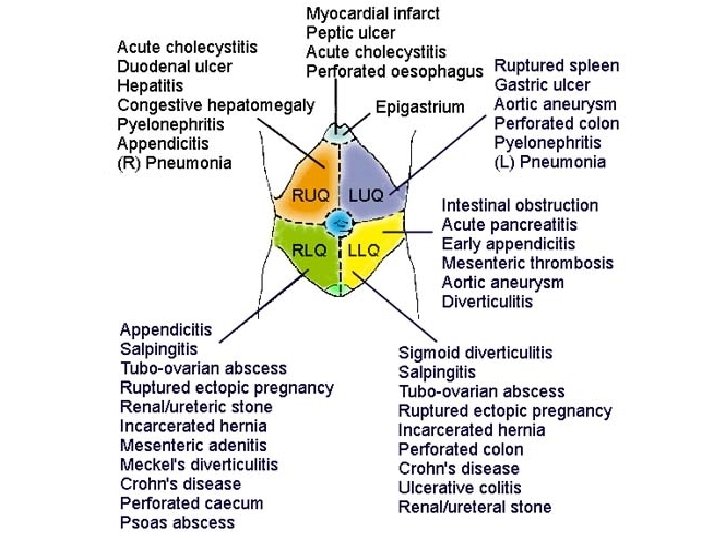

• KLINIKA: - Shenja kryesore eshte dhimbja abdominale e forte qe lokalizohet me veshtiresi nga i semuri. - Dhimbja: fillon ne regionin epigastrik, mund te perhapet edhe ne shpine ose ne shpatullen e djathte, por kryesisht perqendrohet ne kuadrantin superior dexter. - Eshte nje dhimbje me intensitet ne rritje. - Kjo dhimbje pasqyron tensionin dhe inflamacionin e mureve te kolecistes, si pasoje e obstruksionit kalkuloz te duktusit cistik.

• DIAGNOZA DIFERENCIALE: - Appendisiti (ne fazen fillestare) - Pankreatiti - Patologjite renale dexter: infeksion apo kalkul ne ureter: *Anamneza *Ekzaminime laboratorik (urine) *Ekzaminime radiologjike te aparatit urinar

• DHIMBJA: Vjen nga nje peristaltike e sforcuar per te kaluar pengesen. Me shpesh paraqitet rreth umbilikusit ne epigaster, per segmentet e siperme te zorreve te holla dhe ne kuadrantet inferior te abdomenit ne okluzionin e segmentit te poshtem te kolonit

KLINIKA: • DHIMBJA: Fillimisht e moderuar ne forme kolike ne regionin periumbilikal, me pas shnderrohet ne dhimbje te qendrueshme e zhvendosur ne kuadrantin inferior dexter.

EKZAMINIMET LABORATORIKE: - Hemogram: Leukocitoze - Ekzaminimi i urines: per diagnoze diferenciale DIAGNOZA DIFERENCIALE: - Kolecistit - Kolika renale dexter - Ulcer gastroduodenale e perforuar - Okluzion intestinal